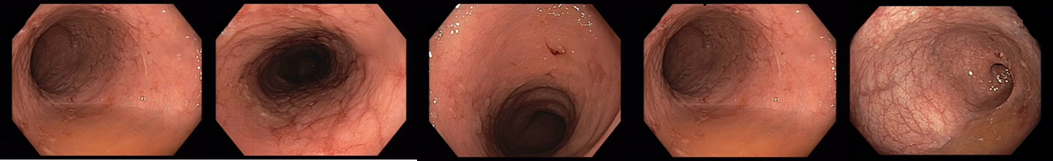

Koloskopie: edém, eroze, ulcerace, zánětlivé polypy v terénu po zánětlivých změn

018/2 Slizniční zhojení. Monoterapie vedolizumabem

Slizniční zhojení

Histologie: lehká porucha architektoniky krypt, může se jednat o pozánětlivé změny. Jiné histopatologické změny přítomny nejsou.